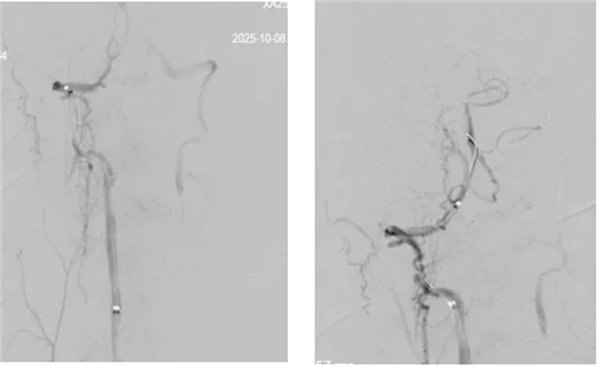

席聰準確鎖定患者基底動脈處血栓,采用抽吸取栓技術快速開通血管,成功取出堵塞部位2cm的血栓。再次造影示:右側大腦后及雙側小腦上動脈再通,右側大腦后動脈P3段以遠閉塞,考慮慢性閉塞,推注替羅非班,血流明顯加快。隨后采用支架植入術開通右側椎動脈開口處,術中影像顯示:支架貼壁良好,無明顯殘余狹窄,顱內血管顯影良好。

術后,患者癥狀明顯好轉,神志清楚,右手無力、視物模糊癥狀明顯改善,術后24 小時可下床活動,NIHSS評分1分,mRS評分2分。